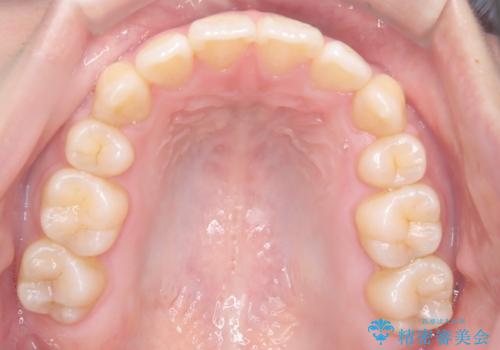

- 八重歯を主訴に来院されました。

左側犬歯が埋伏していましたが、第一小臼歯(4番目の歯)を抜歯したことでできたスペースに牽引し、右側の飛び出した八重歯を含め、歯全体を整列することができ患者様も満足していただきました。